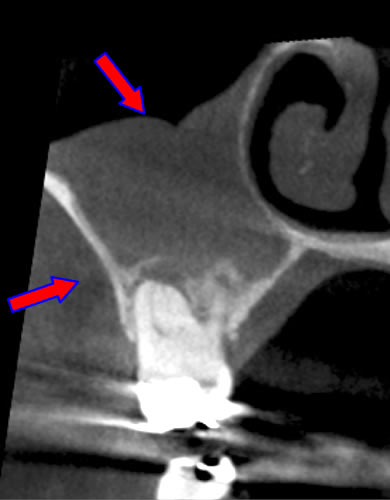

CT画像を見ると根管が2本あることが分かりました。(レントゲンだけでは分かりませんでした。)

| 治療説明 | 右下第2小臼歯、他院で根管治療した後に頬側根尖部から排膿があます。X線CT画像では、根管が2本あり、そのうち舌側が根管充填されていませんでした。顕微鏡下で2根管とも根管充填処置を行い、4ヶ月で、X線透過像は消失しました。 |

|---|---|

| 治療期間 | 6〜24ヶ月 |

| 治療費用 | 150,000〜300,000円 |

| 治療に伴うリスク | 根管内からの治療で根尖病巣が治らない場合は、外科的に根尖病巣を除去する必要があります。 再根管治療を繰り返す場合、歯根の厚みが薄くなり、歯根破折のリスクが高まります。 |